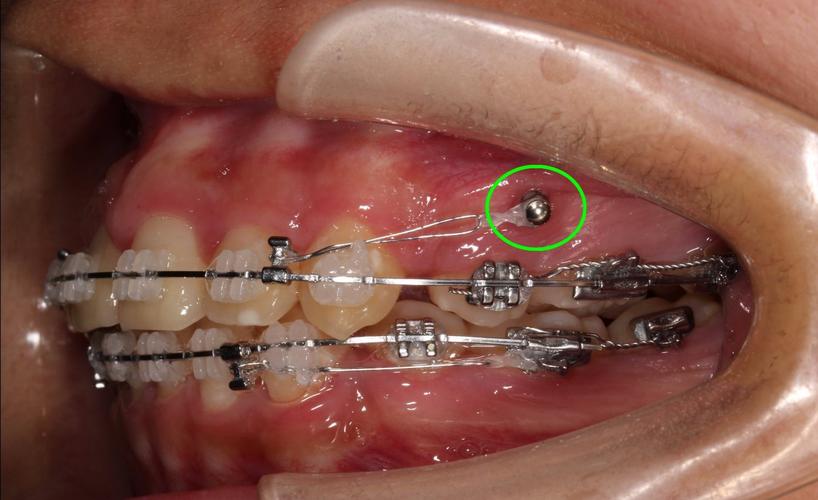

第三步:牙釘的置入與黏合

在局部麻醉下,牙醫會將選定的牙釘,使用特殊的黏著劑或樹脂水泥,穩固地黏合在預備好的根管空間裡。這個過程需要精準的操作和良好的隔濕,以確保牙釘能牢固地結合在牙根內。這時候,麻醉藥的作用下,您通常只會感覺到牙醫在嘴巴裡操作的觸感,而不會有疼痛。